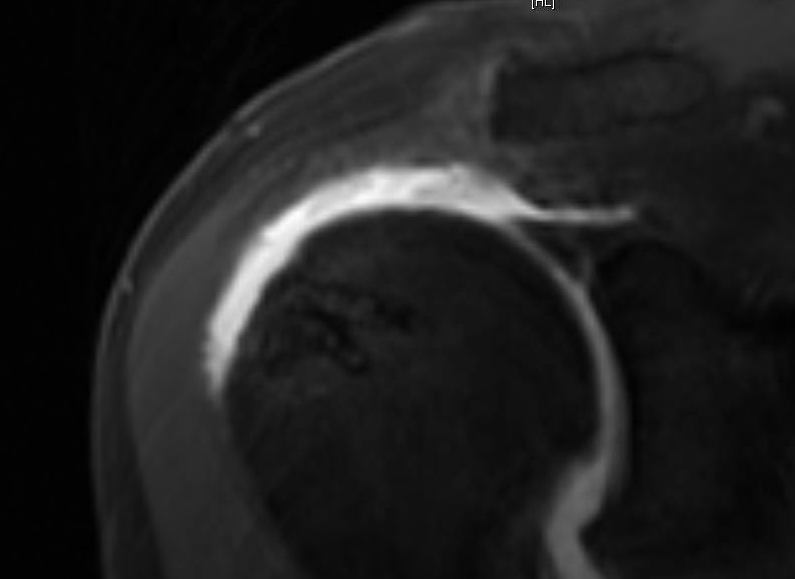

Complications of Rotator Cuff Surgery in Which Bioabsorbable Anchors Are Used AJR

From www.ajronline.org